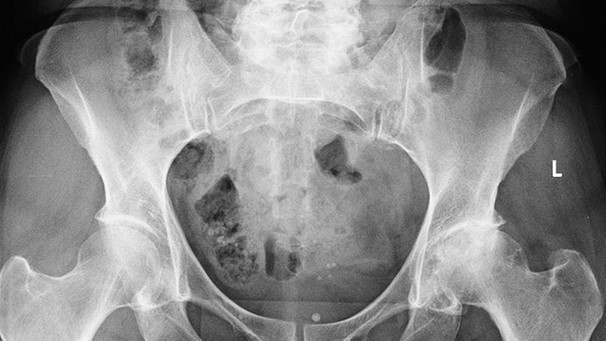

Die häufigsten Ursachen für Hüftschmerzen und Knieschmerzen sind abnutzungsbedingte Veränderungen des Gelenkes sowie auch unfallbedingte Verletzungen  (Knie- und Hüftverletzungen) und Verletzungsfolgen wie beispielsweise Hüftarthrose, Kniearthrose, gelenknahe Knochenbrüche, Meniskusrisse, Kreuzbandrisse.

Behandlungen von Hüft- und Kniegelenksverletzungen und degenerative abnutzungsbedingte Leiden sind eine unserer Spezialitäten, so zum Beispiel Kunstgelenkersatzoperationen an Hüfte und Knie, als auch Knochenbruchbehandlungen insbesondere hüftgelenksnahe Frakturen, Oberschenkelbrüche oder auch Knochenbrüche unter Mitbeteiligung des Kniegelenkes. Eine unserer weiteren Spezialitäten ist die Behandlung von Meniskus- und Kreuzbandrissen. Die Entwicklungen auf diesem Fachgebiet sind enorm vorangeschritten, sodass heute viele Eingriffe in entsprechender arthroskopischer oder minimal-invasiver Technik durchgeführt werden können. Dies führt in der Regel zu bedeutend kürzeren Spitalaufenthalten. Für weitere Informationen wenden Sie sich an unsere Praxis, kontaktieren uns via Kontaktformular oder entnehmen Informationen aus den nebenstehenden Links. Doch was ist eigentlich Arthrose? Lesen Sie auf diesem Link weiter!